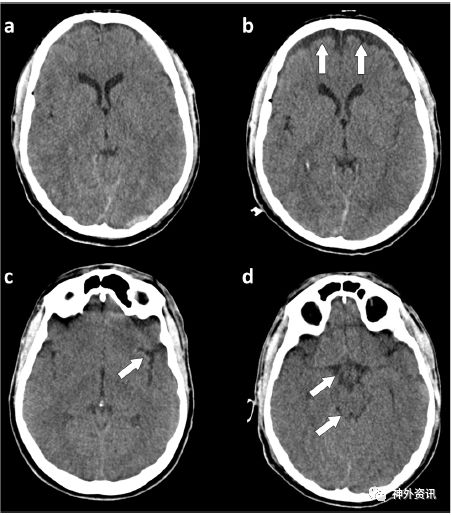

该项多中心回顾性研究纳入33例创伤性和非创伤性颅脑损伤后或药物治疗效果差,出现迟发性ICP增高的患者。通过影像学检查诊断为交通性外部脑积水(图1),对患者进行腰穿外引流治疗。记录患者ICP值的变化以及腰穿外引流后的并发症。

图1. CT显示典型的交通性外部脑积水。a.入院时头颅CT扫描;b.腰穿外引流前脑CT扫描,显示额部液体潴留(白色箭头);c.非正常的大脑外侧裂;d.基底池。药物治疗后ICP仍高于30mmHg时需要进行腰穿外引流。